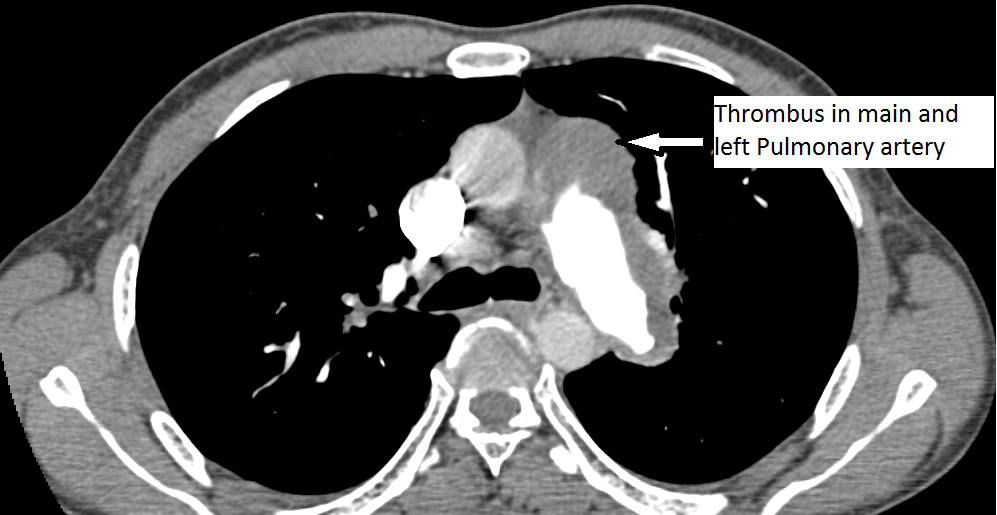

The authors present a case of CTEPH. The patient was a 35-year-old man presenting as an outpatient with complaints of severe progressive dyspnea. He was diagnosed with pulmonary embolism in the past and has been on anticoagulation for more than three years. He has had CT scans and chest x-rays in between. Multiple transthoracic echocardiograms have been performed with evidence of slowly declining right ventricular function. This time, he presented to the cardiac surgery service with a severely dilated and dysfunctional right ventricle. He had been on diuretics and vasodilator treatment but had mild to no improvement. After a thorough review, the authors decided to perform a pulmonary thromboembolectomy. The CT scan images show a dilated RV and intravenous contrast reflux in the inferior vena cava (Figures 1-4). The thrombus can be seen starting in the main pulmonary artery and almost completely occluding it. The thrombus extends into the bilateral pulmonary arteries.